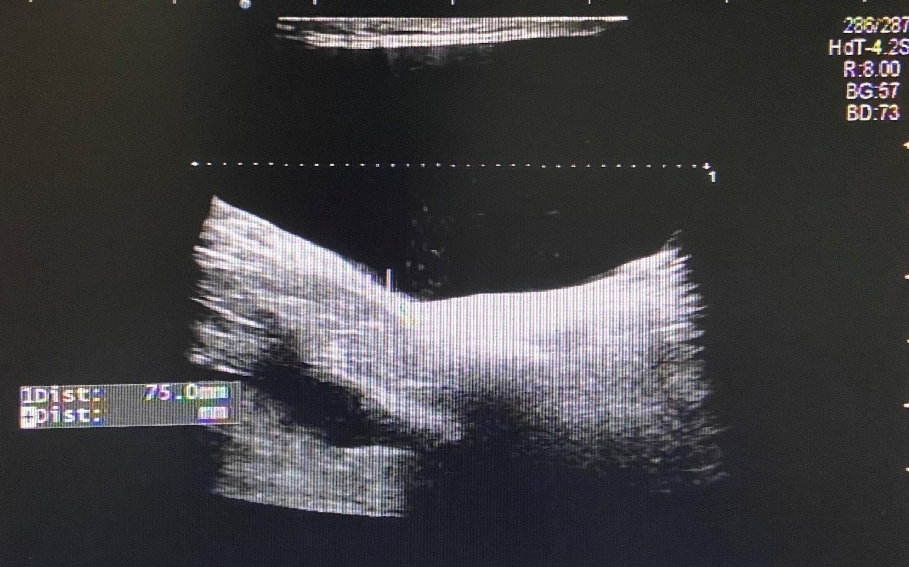

Case 5

图 10 左侧腹股沟区包块

超声所见

左侧腹股沟区见范围约 6.8cm×2.1cm×1.3cm 无回声区,透声一般,可见分隔,增减腹压未见明显变化。右侧腹股沟区未见明显异常回声。

超声提示

左侧腹股沟无回声区,子宫圆韧带囊肿?

术后证实为左侧子宫圆韧带囊肿合并腹股沟斜疝